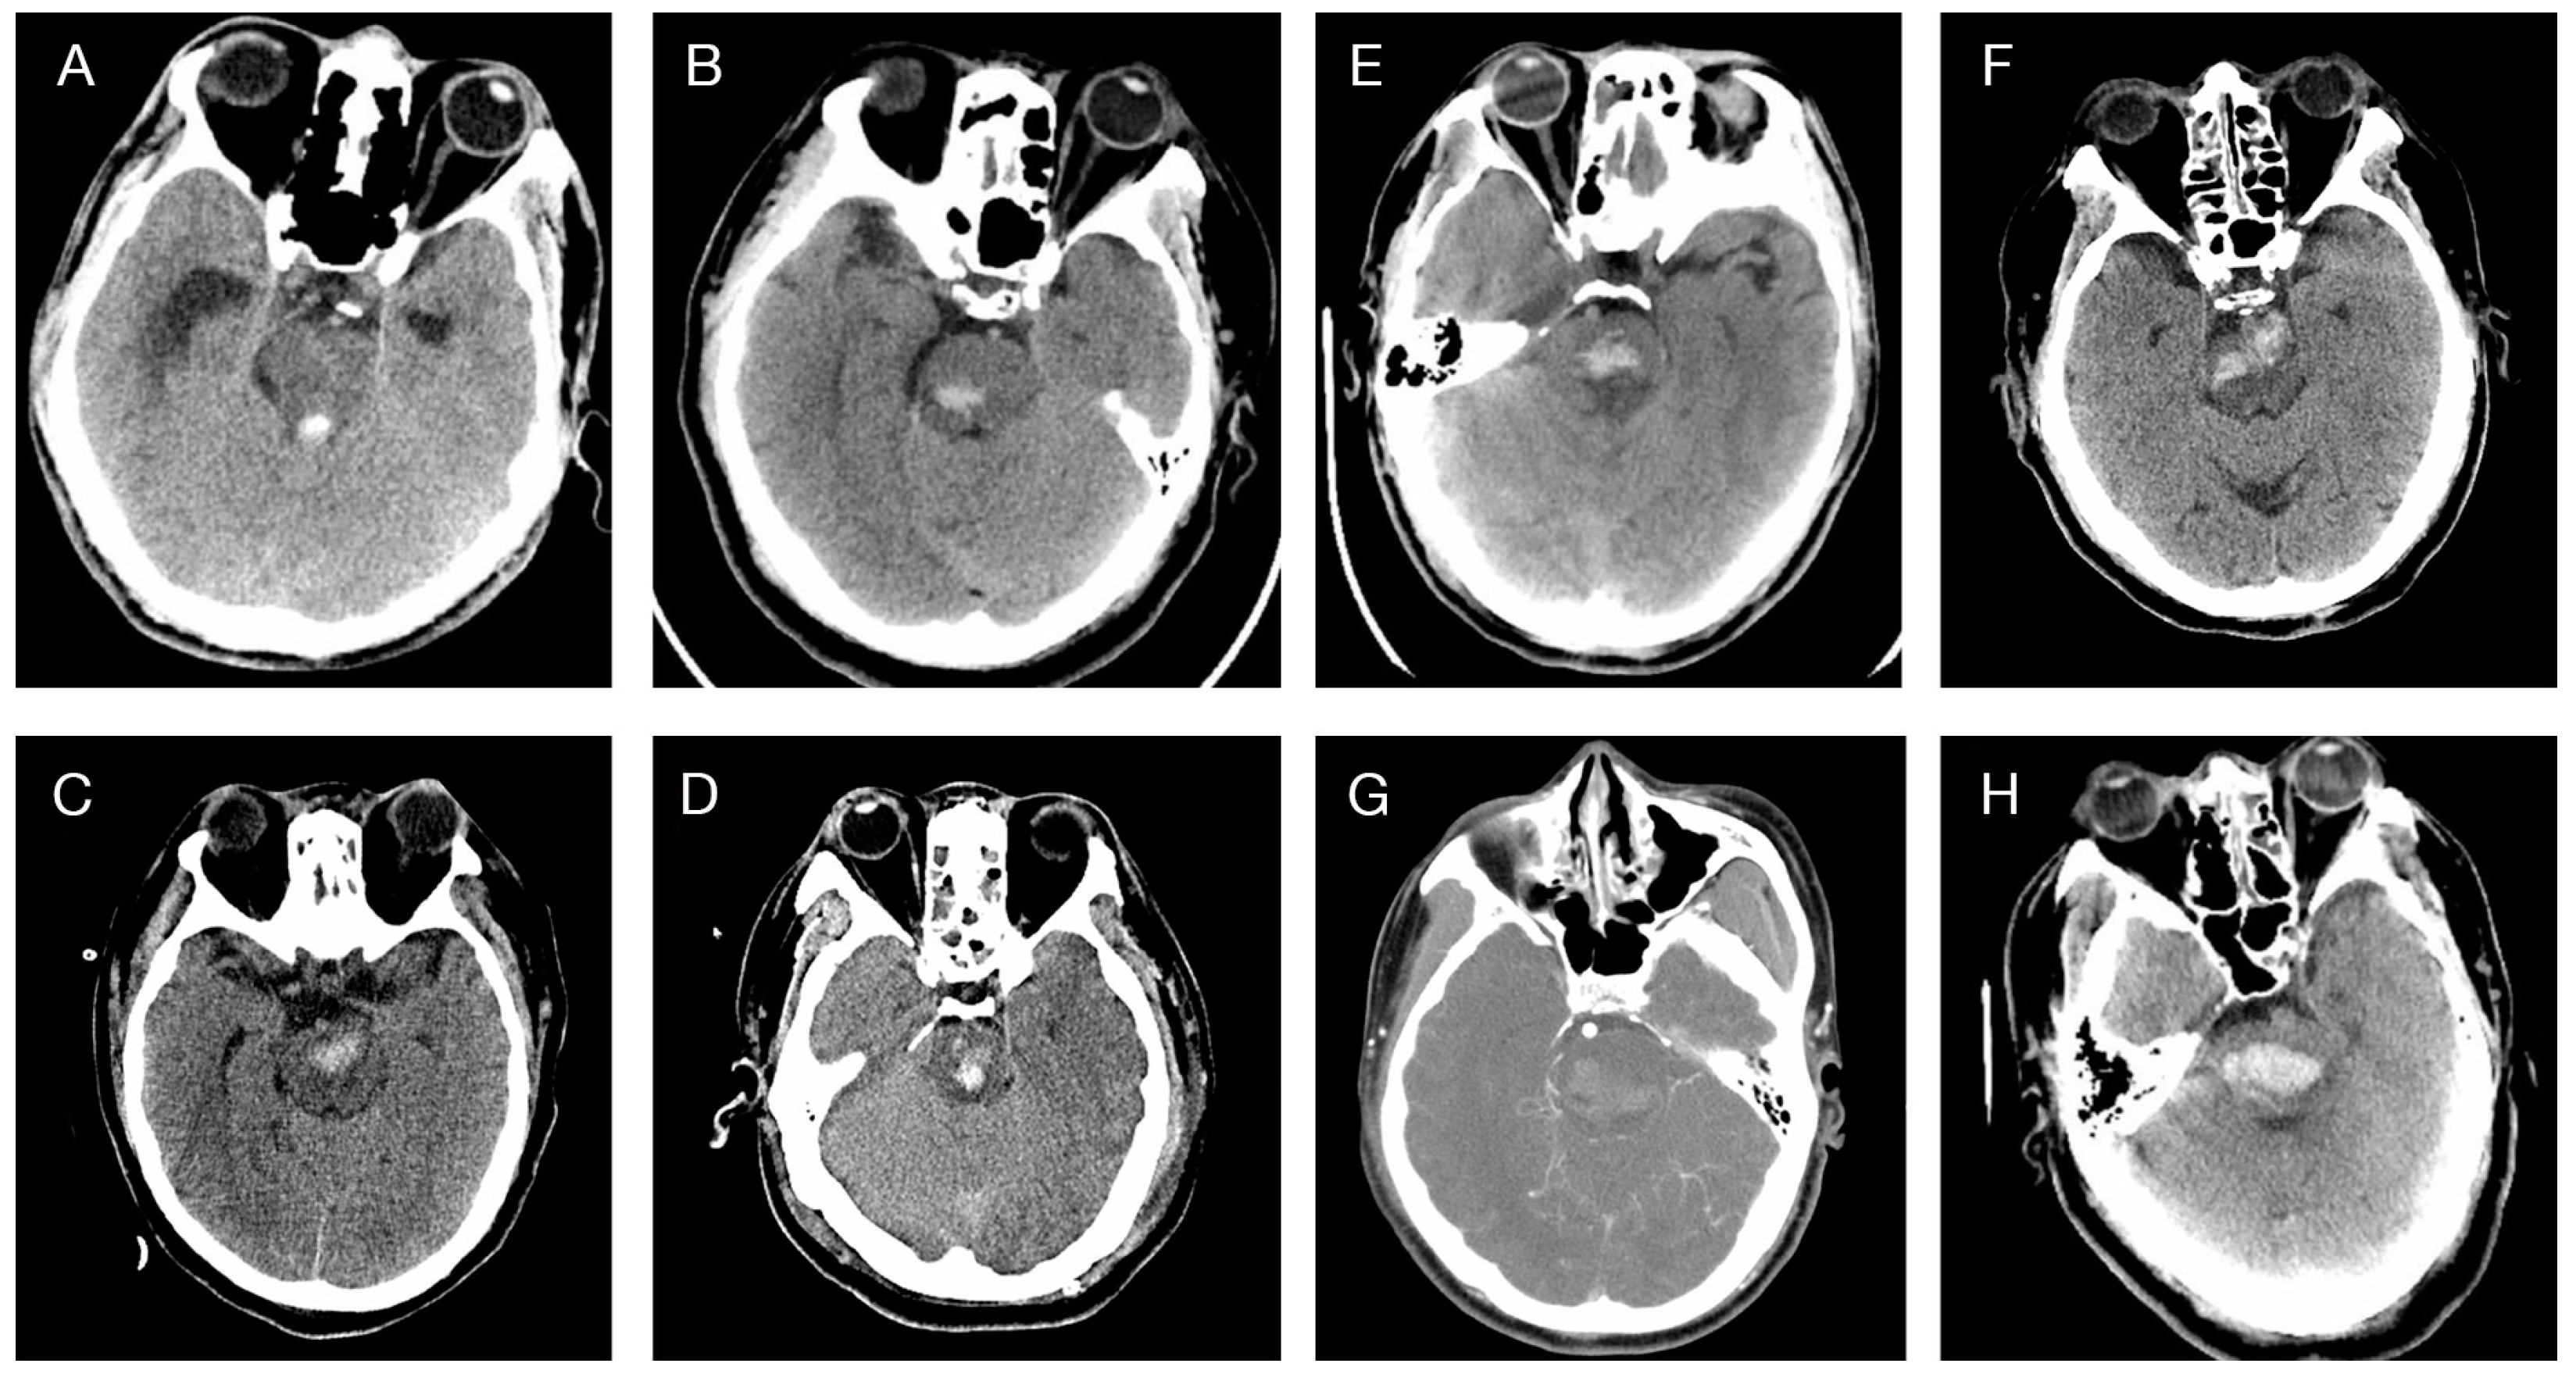

- Chung, C.S.; Park, C.H. Primary pontine hemorrhage: A new CT classification. Neurology 1992, 42, 830–834. [Google Scholar] [CrossRef] [PubMed]